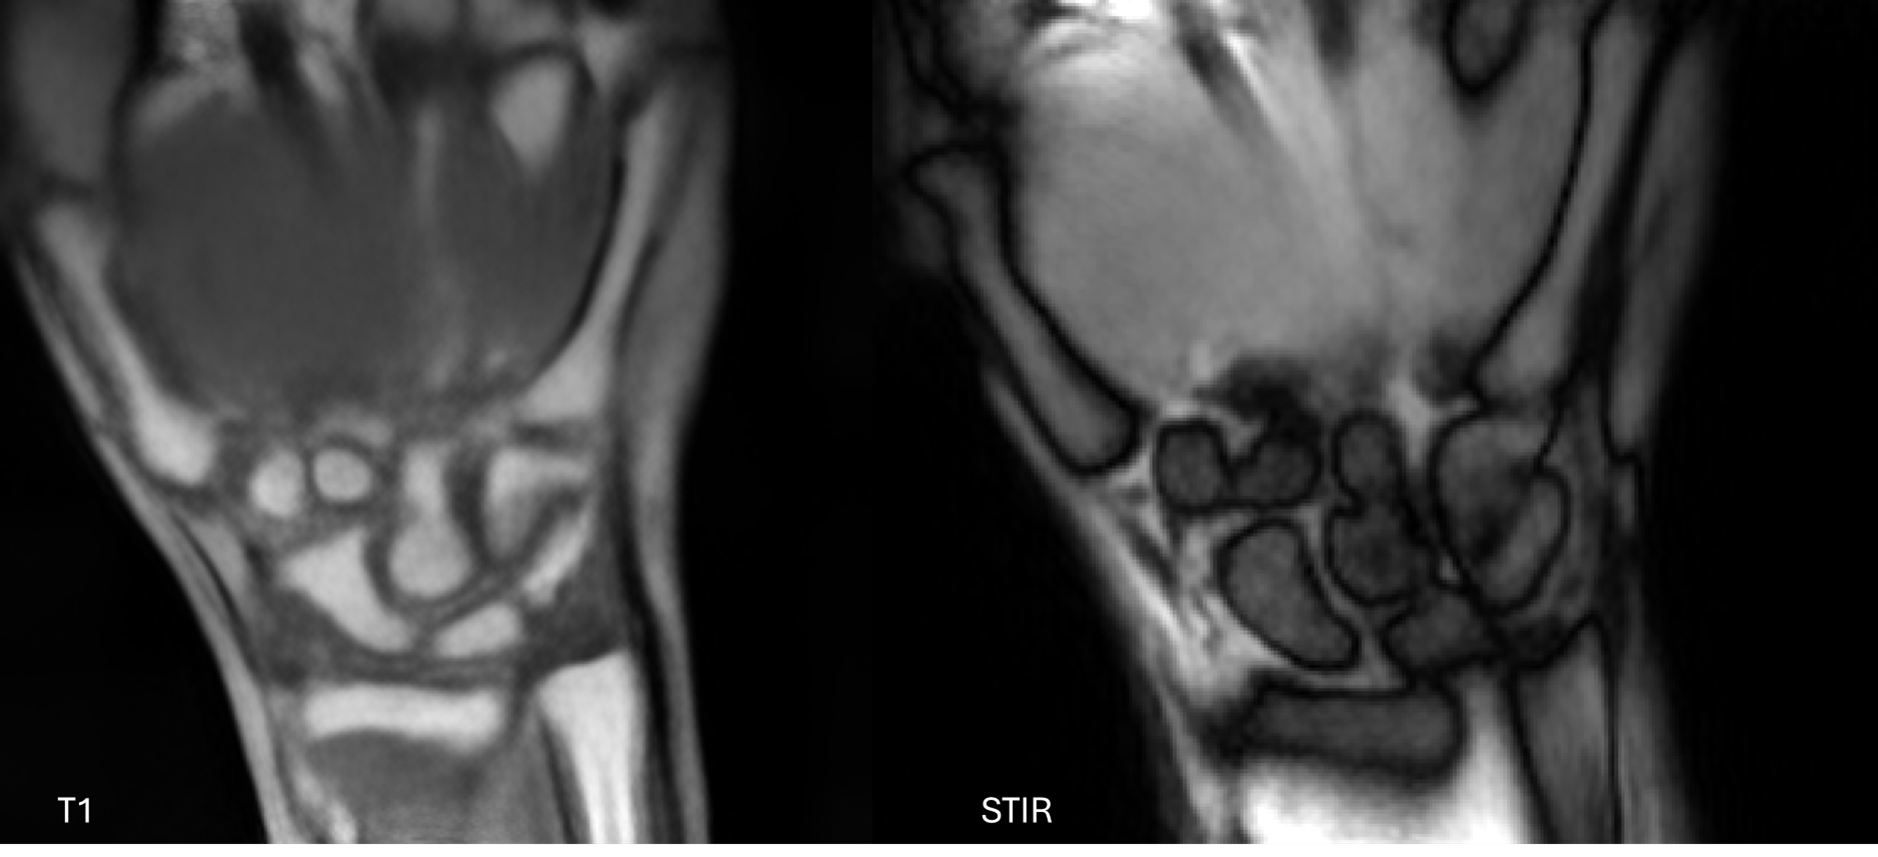

Hands Image

Exceptional soft tissue contrast for evaluating rheumatologic conditions, tendon injuries, and small joint abnormalities. The Next MRI’s dedicated coils optimize signal-to-noise ratio for these specialized applications.